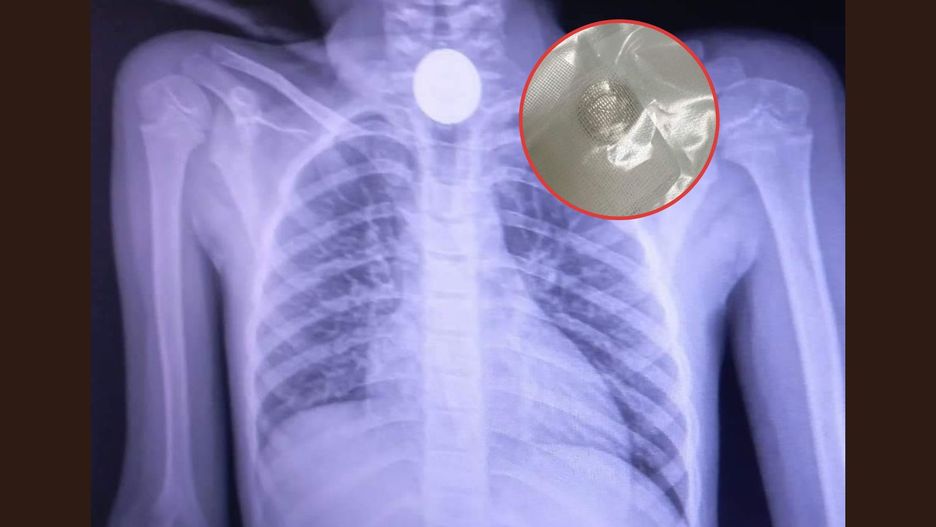

Na facebookowym profilu Wojewódzkiego Szpitala im. Św. Ojca Pio w Przemyślu pojawiła się fotografia przedstawiająca zdjęcie rentgenowskie, na którym widocznie odznacza się okrągły przedmiot. To jednozłotowa moneta, która utkwiła w przewężeniu przełyku sześcioletniej dziewczynki.

Przez połknięcie monety dziecko miało odruchy wymiotne i nie mogło nic przełknąć, nawet własnej śliny. Trafiło na SOR, gdzie konieczny był zabieg ezofagoskopii.

- Polegał on na tym, że przez usta lekarz wprowadził sztywny wziernik i specjalnymi kleszczykami wyciągnął przedmiot. Procedurę wykonuje się w znieczuleniu ogólnym. Na szczęście wszystko dobrze się skończyło i pacjentka już następnego dnia została wypisana do domu - mówi dla portalu nowiny24.pl Paweł Bugira, rzecznik Wojewódzkiego Szpitala w Przemyślu.